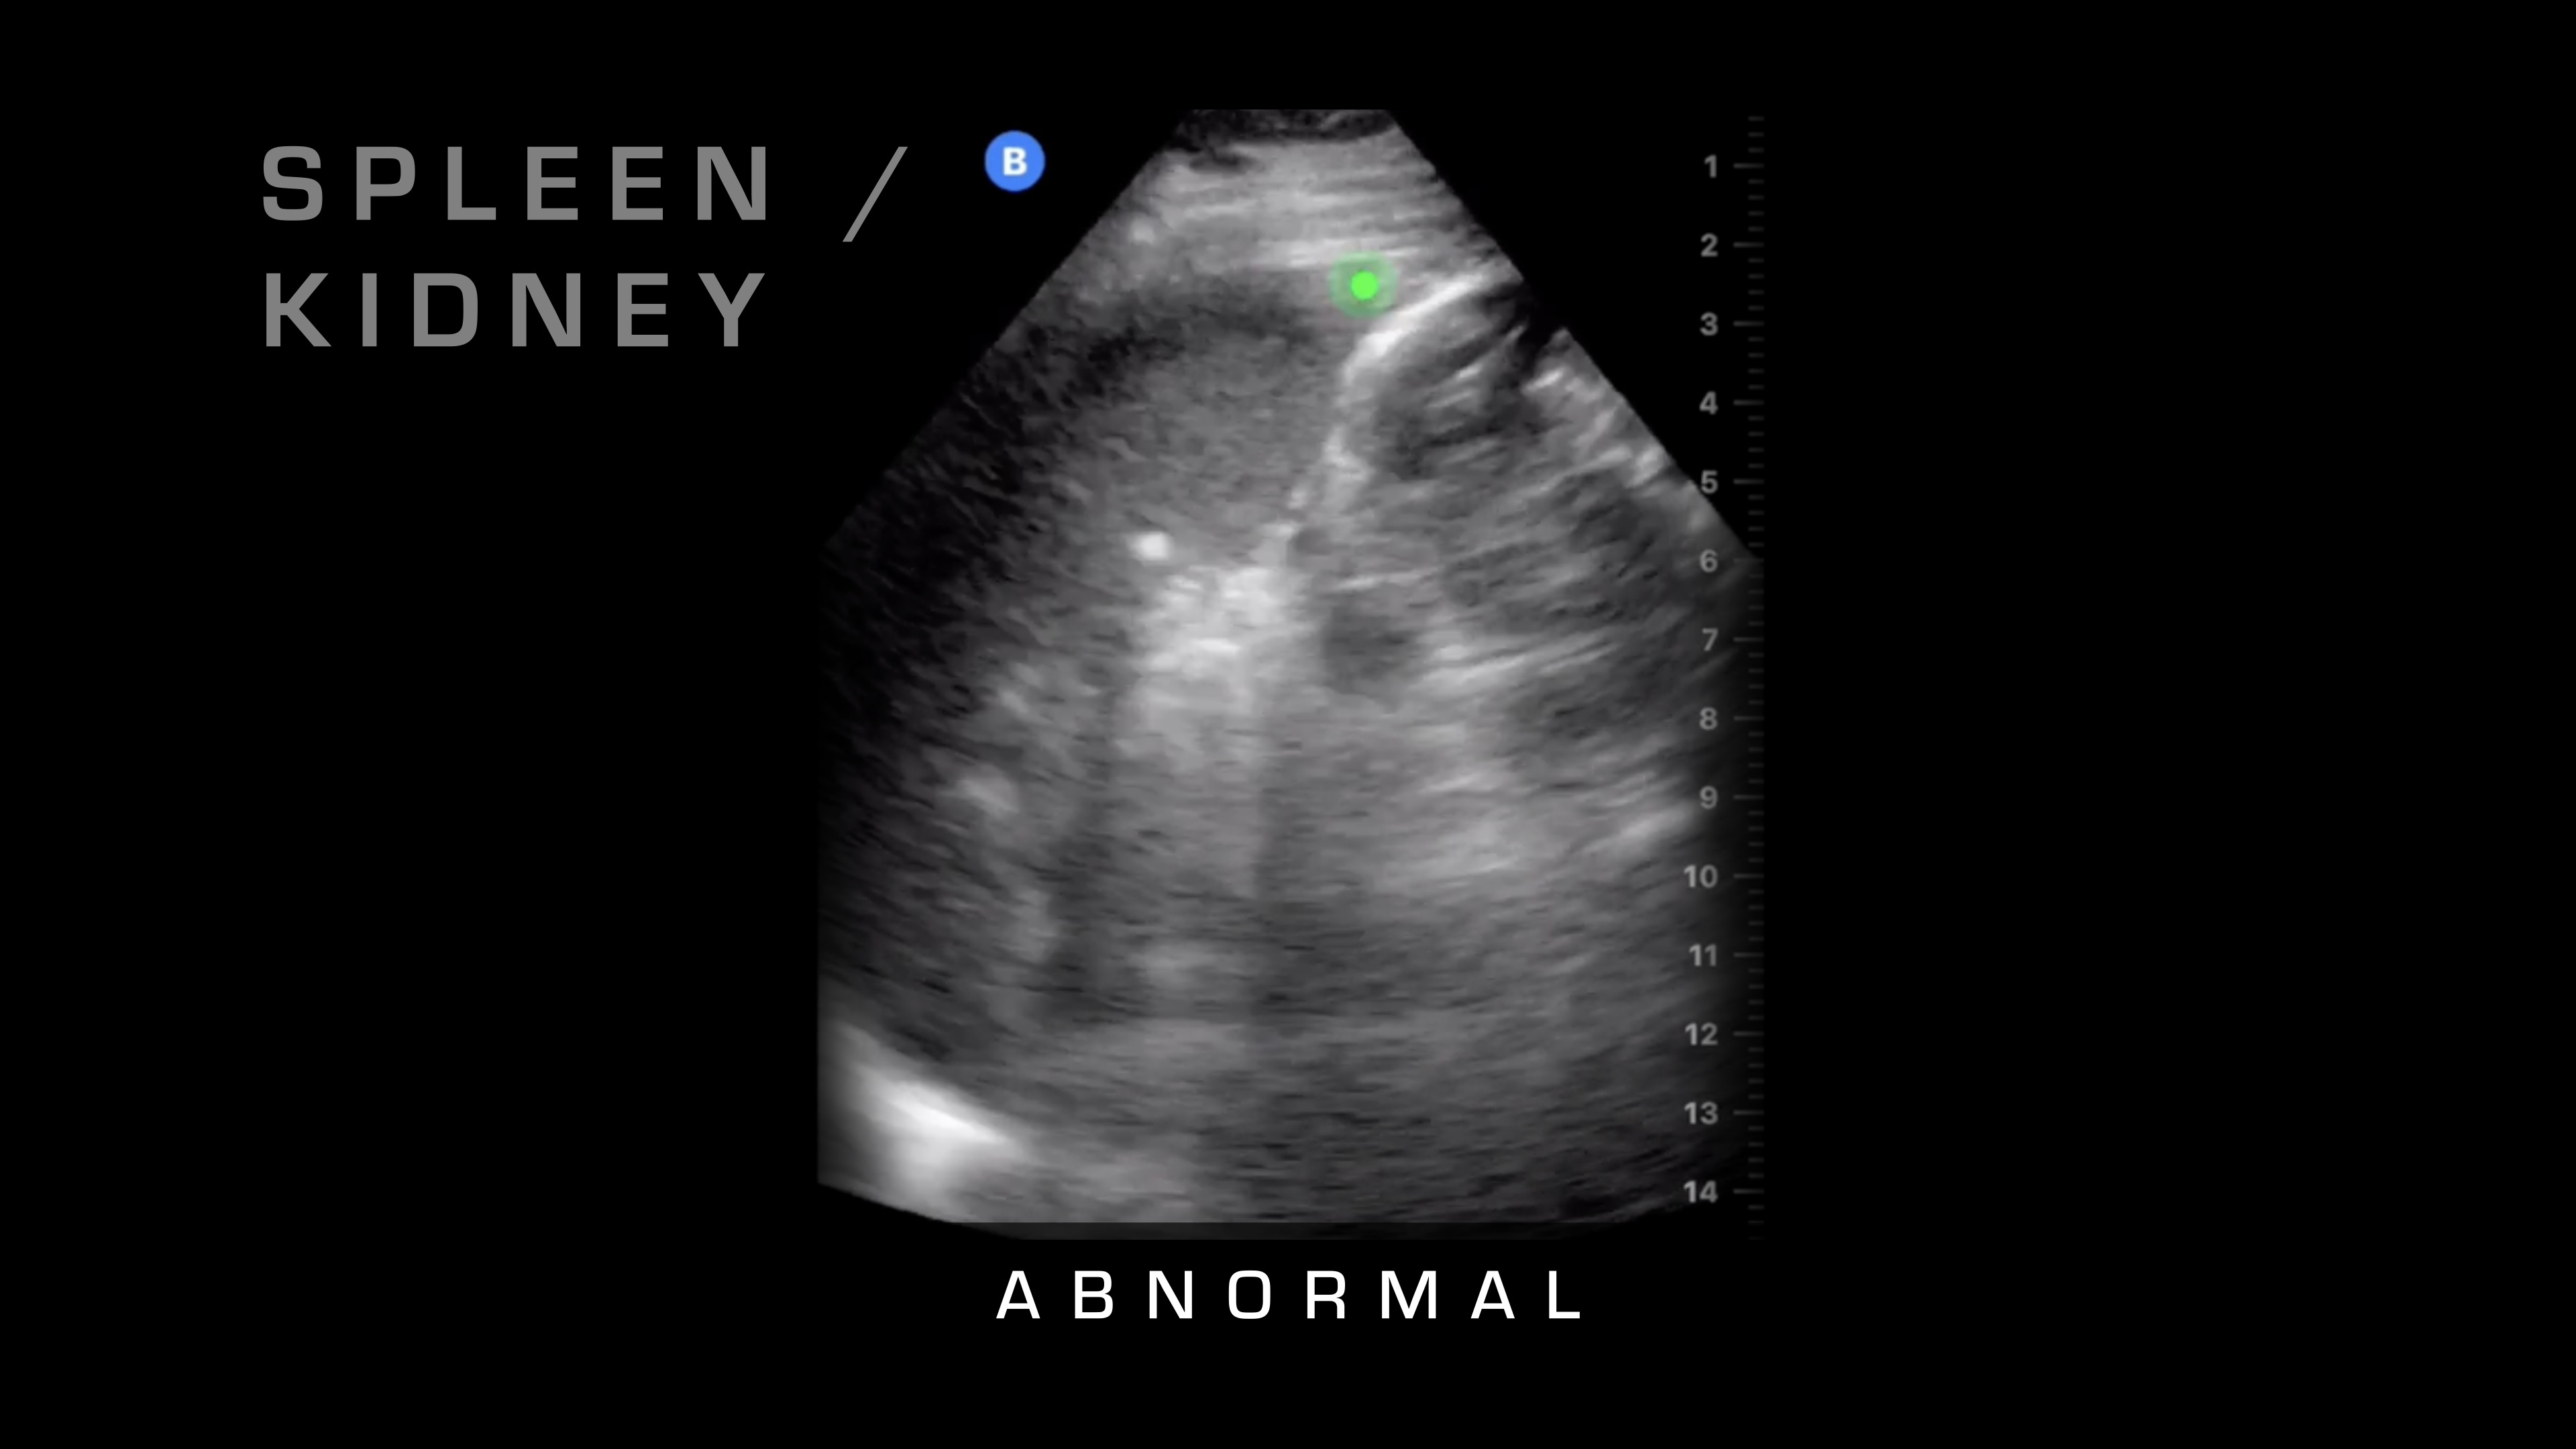

Spleen and Kidney

Then the first thing that I'm going to do is I'm going to place it down over here. What am I looking for here? I'm looking for the spleen and the kidney where they intersect. Sometimes you can tell if it's a cracked or a fractured spleen, if there's a big hematoma within the spleen, but really, we're looking for free fluid in the abdomen, which is going to be blood.

So what does blood in the abdomen look like? Blood looks like a black spot because, as the ultrasound waves penetrate through, it travels with minimal reflection, so it's just going to look like a black spot.

So I'll show you some normal, and then here's an abnormal one where you can see the fluid that's built up between the spleen and the kidney.